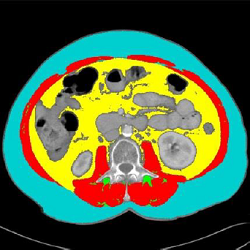

F3 (Tint)

Good for checking errors and/or

out of place pixels

F4 (Over)

Used for presentations

|

Warning: Even though they are not visible, you can still edit the TAG values in this mode

Note: With F2 and F3, you can change the color opacity

with the "shift +" and "Shift -" keys.